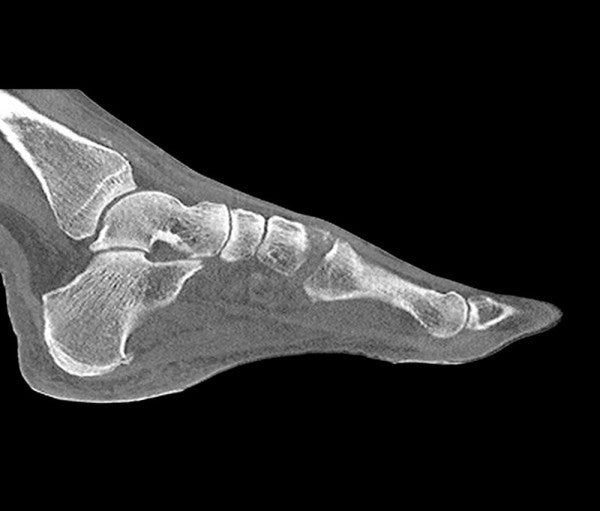

The Anatomy Phantom Models for CT, X-Ray, and Radiation Therapy offer healthcare students an authentic training experience with a non-contrast agent on a model. These anatomy phantom models accurately replicate tissue contrasts, providing a lifelike representation during imaging and radiation sessions.

The anatomy phantom models were created using state-of-the-art technology and are based on actual patient data, ensuring authenticity. They accurately display bones, vessels, and soft tissue with realistic values at 120 kVp tube voltage in CT scans. If used with different tube voltages, such as 100 kVp, the CT values can be adjusted for proper calibration.

The phantom models exhibit realistic tissue contrasts in X-ray imaging, and air spaces are filled with a material measuring approximately -80 Hounsfield units.